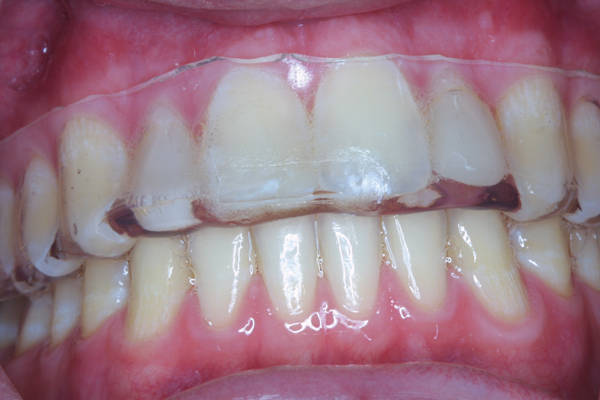

(13.) Retracted view of a patient who had been using tray application of 10% carbamide peroxide for over a year to clean the braces as well as bleach the teeth.

Figure 13